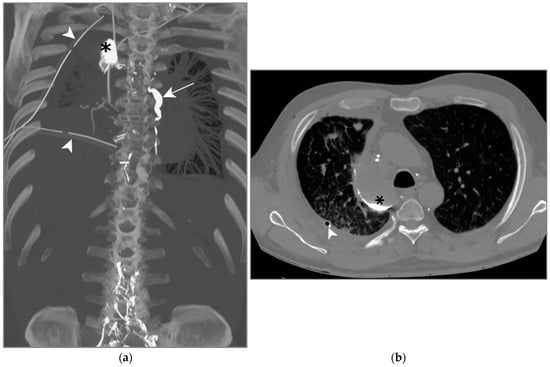

On post-operative day 4, a high-output right chylothorax was diagnosed (>1500 mL/d). TPN was immediately begun and maintained for 10 days; high-volume leakage persisted (Figure 8a,b). On day 10, the patient underwent an LL which showed extravasation of contrast agent into the right pleural cavity. Three days after the LL, the drain output had diminished to less than 100 mL/d, allowing drain removal on day 5. The LL was successful in treating this one-sided post-operative chylothorax.

Figure 8.

Patient D. The axial CT plane through the upper pulmonary lobes with magnification on the right hemithorax (b); the maximal-intensity projection of the CT scan reconstructed in the coronal plane (a). (a,b) The presence of Lipiodol in a right pleural effusion along the mediastinum and in its declive portion (white arrows). Thoracic drainage with a pleural catheter (white arrowhead) is shown.